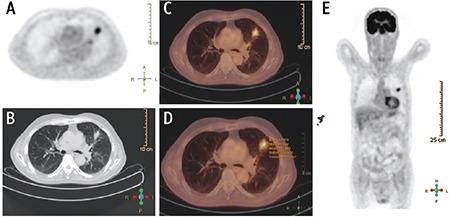

SPN diameter, SUV, metabolic tumor volume (MTV), total lesion glycolysis (TLG), and density were significantly higher in the malignant group. SUV, MTV, TLG increased in direct proportion to the diameter. There was no a significant difference between GGO, PS, and solid nodules in terms of SUV values. MTV and TLG values increased in parallel with the density of the nodules, but this increase was only significant in the malignant group. There was a significant difference between SPNs <2 cm and SPNs ≥2 cm in terms of MTV, while there was no difference in terms of SUV. The cut-off value determined by the ROC curve was found to be 4.39 for SUV, 7.33 mL for MTV and 31.88 g for TLG. The cut-off values for SUV of solid and subsolid nodules were close to each other, but cut-off values for MTV and TLG were higher in solid nodules.

SUV, MTV, and TLG are affected by diameter and attenuation. We suggest using different MTV and TLG cut-off values for solid and subsolid nodules, but we suggest using same SUV values. MTV can be a more reliable parameter than SUV in prediction of malignancy in smaller nodules.